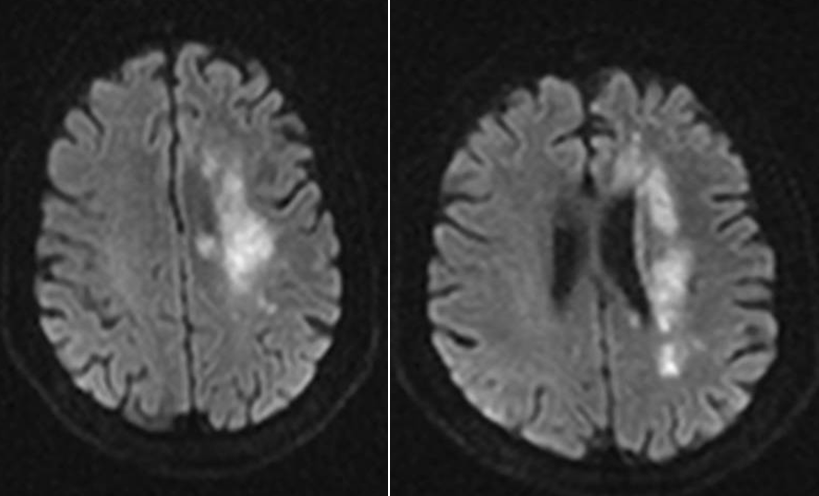

既往影像检查

导丝怎么扩【载药时代 球扩天下】NOVA DES®颅内药物洗脱支架在颈内动脉颅内段重度狭窄中的应用体会二例!_https://www.jmylbn.com_新闻资讯_第3张

DWI

导丝怎么扩【载药时代 球扩天下】NOVA DES®颅内药物洗脱支架在颈内动脉颅内段重度狭窄中的应用体会二例!_https://www.jmylbn.com_新闻资讯_第4张

MRA

重要影像结论:左侧基底节区、放射冠区新发脑梗死;多发脑血管狭窄